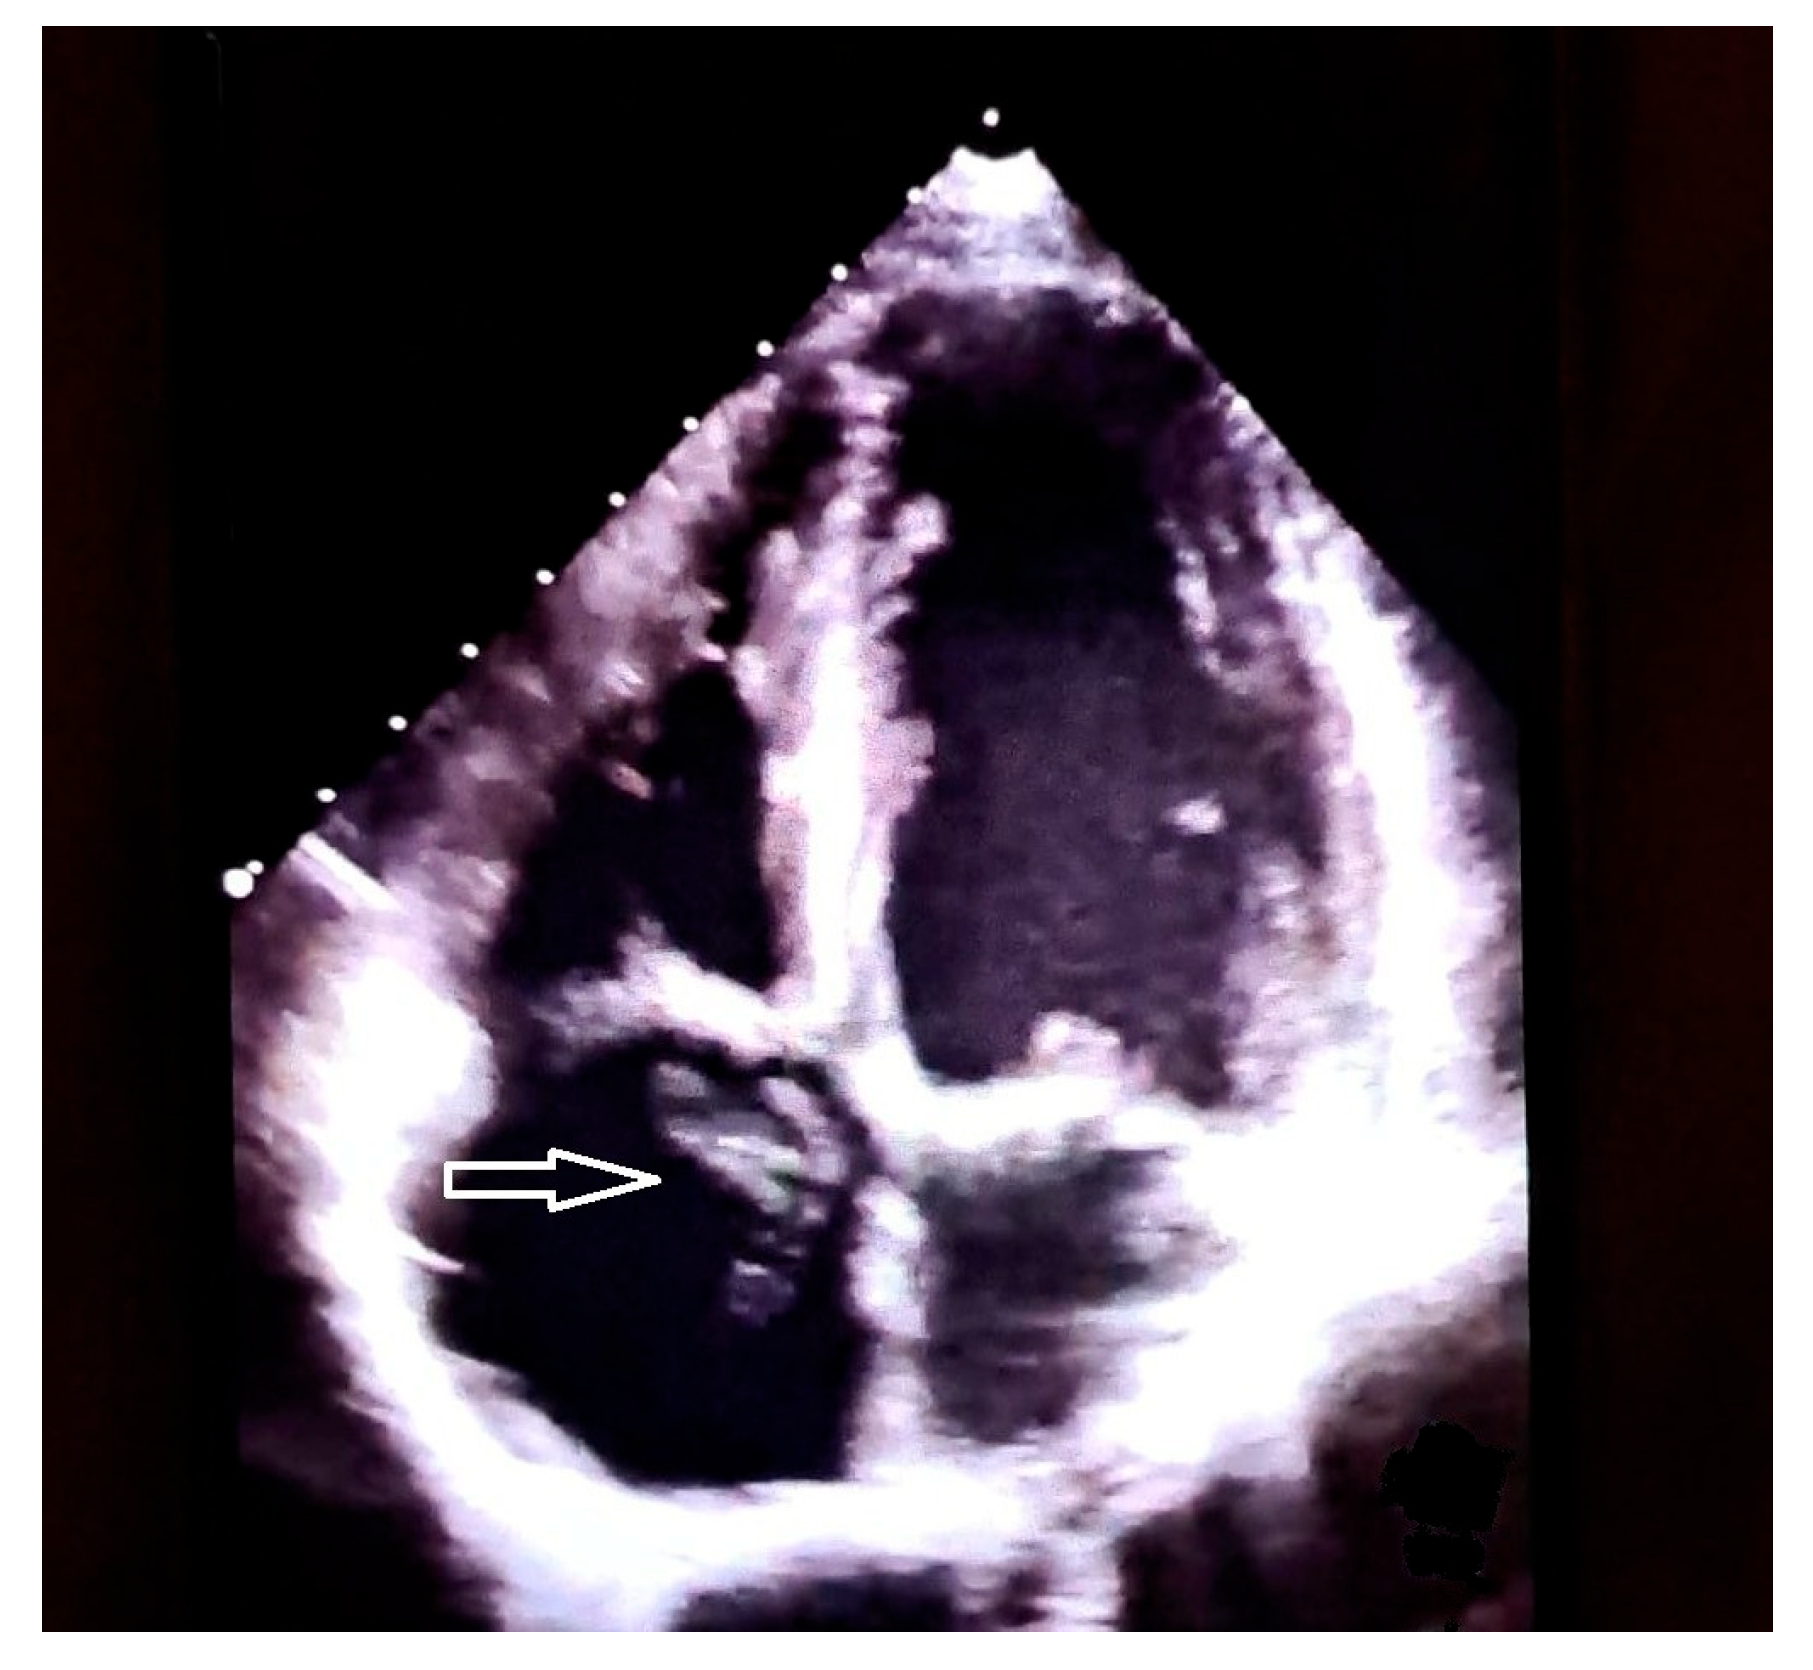

- Franco, E.; Rovera, C.; Moretti, C.; Bassareo, P.P. Arrhythmogenic Right Ventricular Cardiomyopathy and Cor Triatriatum Dexter: An Unreported Association. Clin. Case Rep. 2025, 13, e71159. [Google Scholar] [CrossRef]